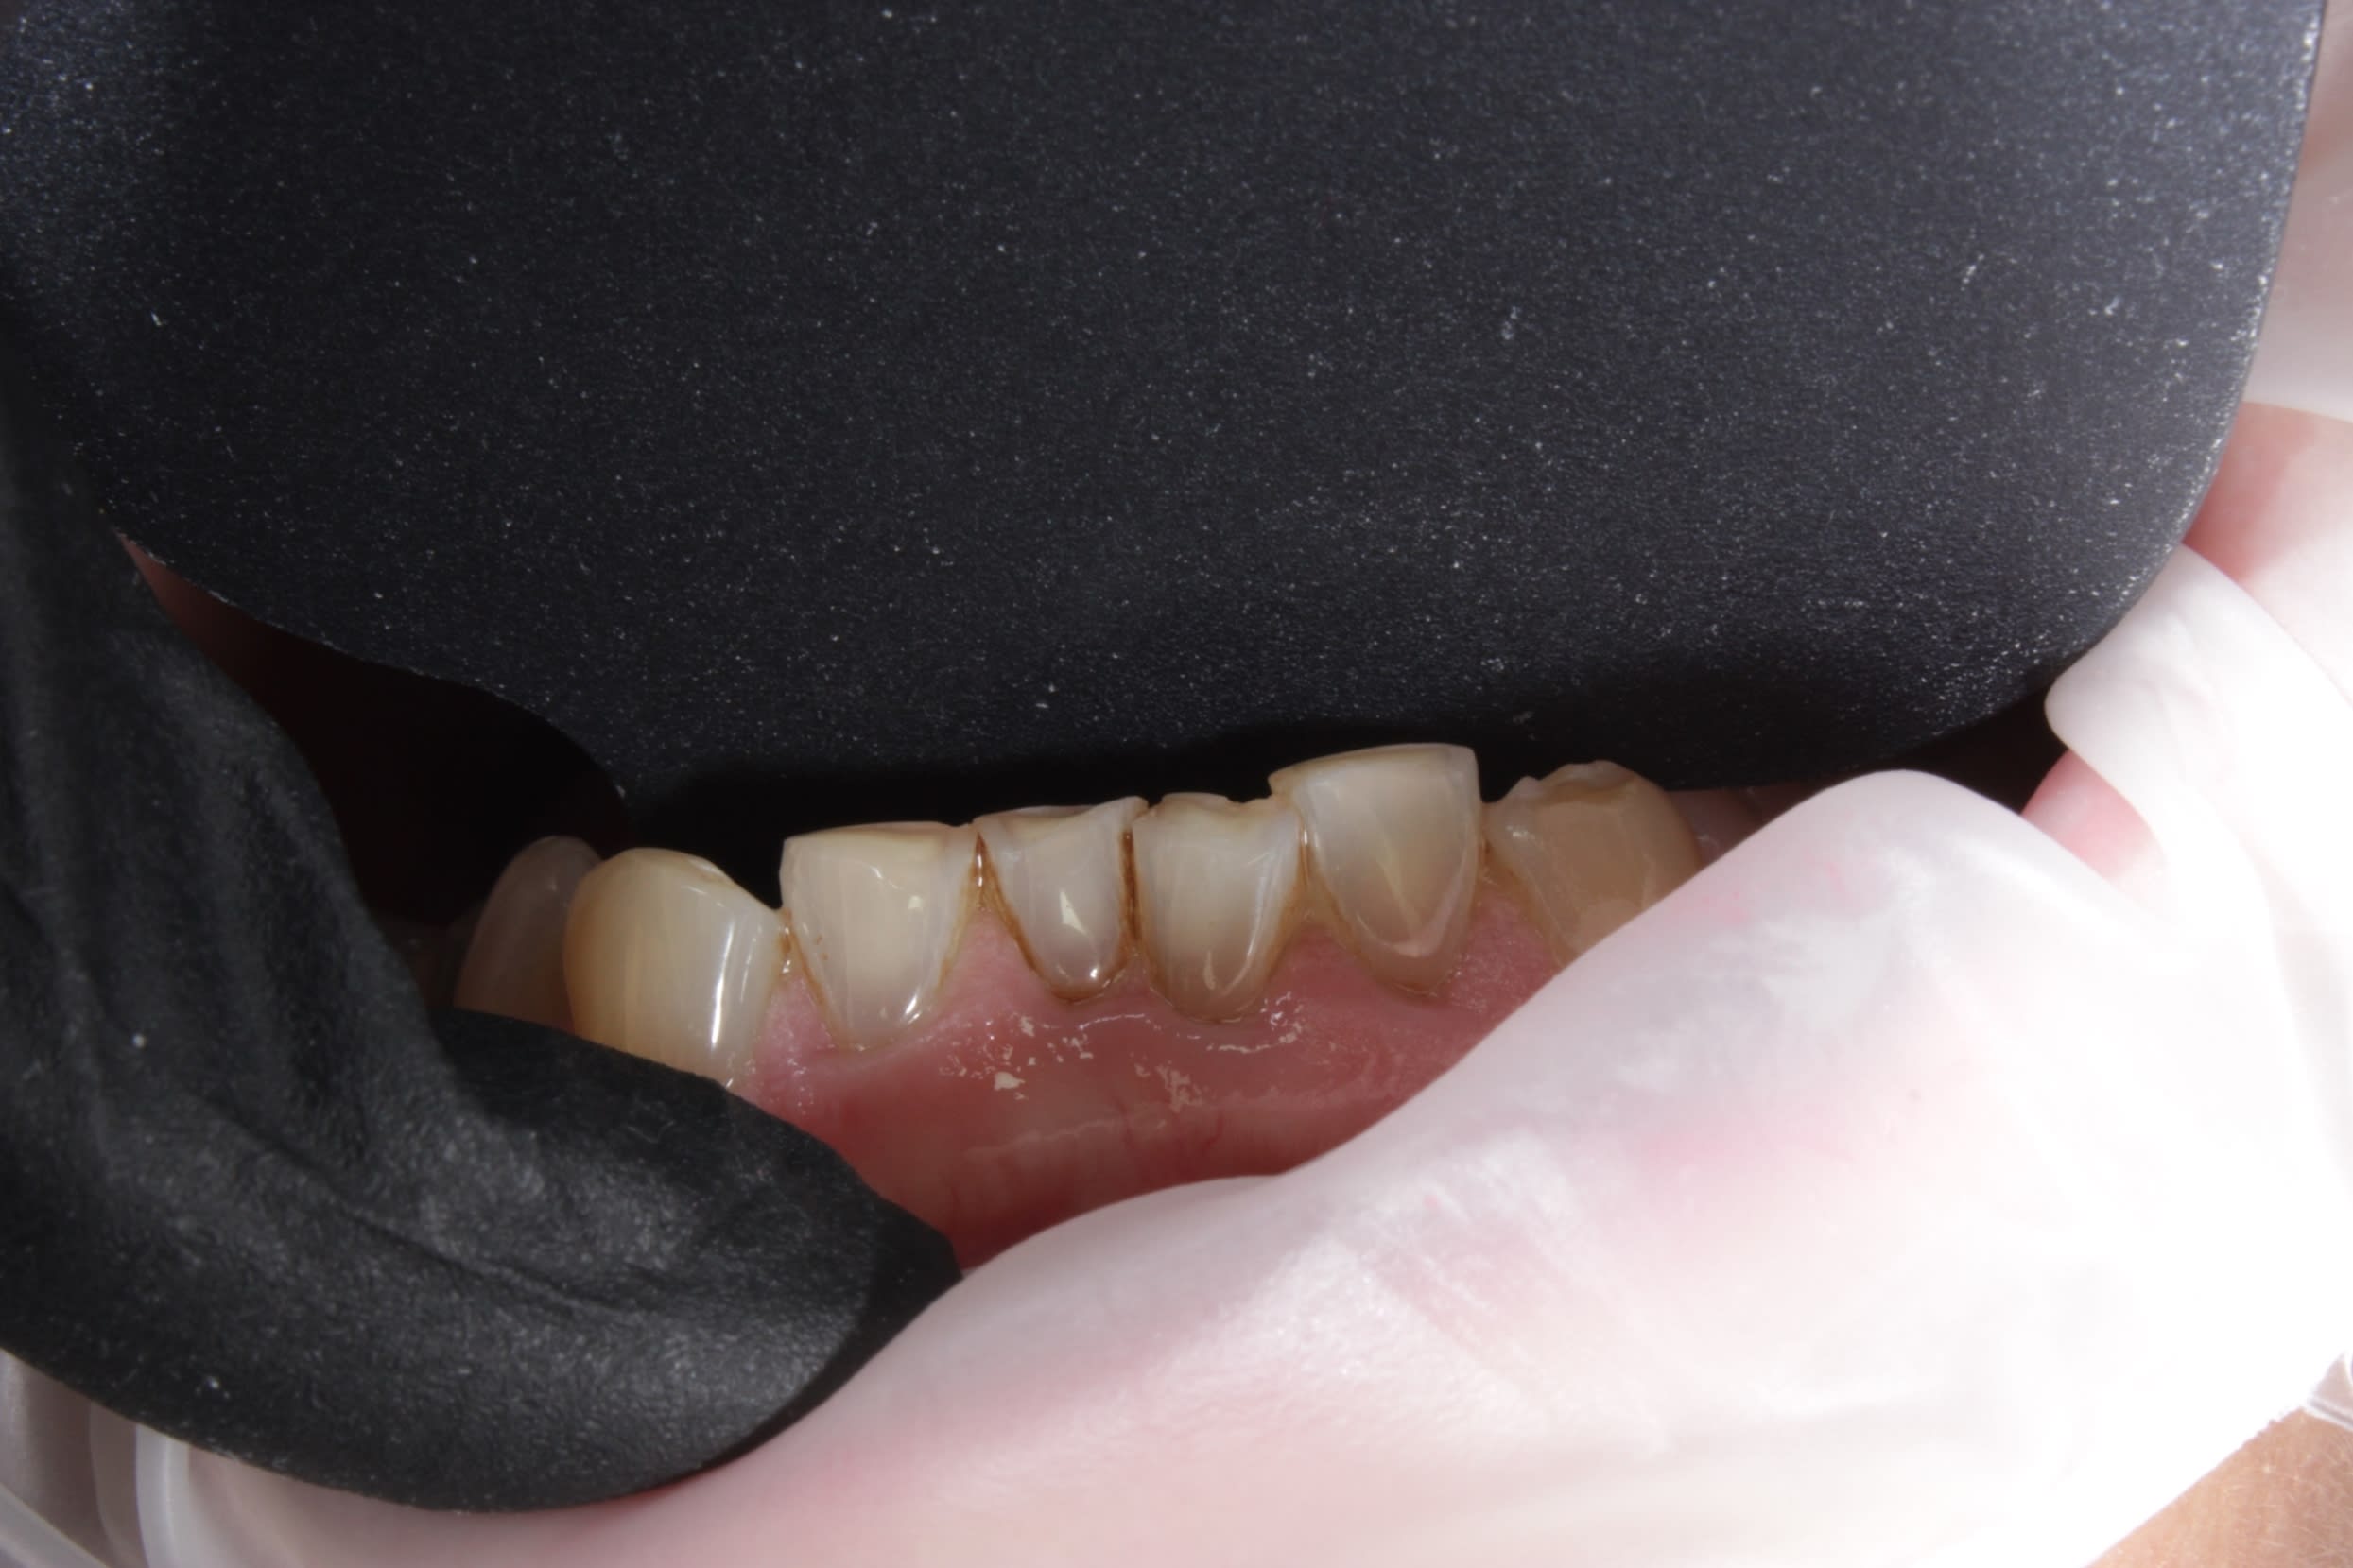

aux vues des usure de 12 et 11 , on y voit bien la trace de la double occlusion dont je parlais .

et au delà de la classe 2 il doit ily avoir une interférence au fond secteur 20 , je dirais la 27 .

Depuis le début tout le monde semble certains d'avoir à faire à une classe II/2, alors que les rapports dentaire sont en classe 1 et que l'angle goniaque semble bien ouvert. On note des toris vestibulaires marqués sur les blocs incisivo-canin, une occlusion palatine sur 15, crête marginale molaires décalées ( tiens peut être plus la 37 que la 27 qui merdoie ;-)), des reconstitutions molaires plates. Ce cas mérites d'être initialement géré avec une vision occlusale avant qu'elle soit orthodontique (ce qui n'exclu pas évidement l'ortho) et forcément prothétique pour remettre le secteur postérieur en fonction. Et je ne vois pas pourquoi la vestibulo version des incisives sup entraînerait une prochéilie alors qu'elle trouve surtout sont origines au niveau des toris bien proéminent

Mais en admettant que les milieux soient décalés , tu penses sérieusement qu' en lui reculant toutes les dents ou même que d un côté pour rattraper un point inter incisif d'une mamie de 52 ans , ça va lui changer son esthétique et lui donner un sourire de star alors qu elle a des dents de toutes les couleurs et usées qu on dirait un vieux piano,

Voilà, on est donc bien dans une interférence qui explique l encombrement qui a créé le sur- guidage incisif .

A mon avis cette interférence est d origine iatrogène a savoir le compo palatin de la 22 .